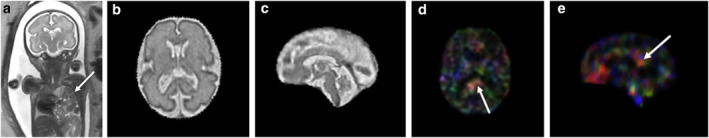

Objective: To evaluate differences in diffusion tensor imaging (DTI) parameters in the brain between fetuses with congenital diaphragmatic hernia (CDH) and age-matched controls.

Method: This retrospective IRB-approved study included fetal MRIs for CDH and gestational age (GA) matched controls with lung pathology other than CDH with normal fetal brains. Fetal DTI data were acquired in 15 noncollinear diffusion-weighting directions with the b-value at 600 s/mm2 (1 b0). Slice-to-volume registration (SVR) was employed to correct for motion artifact.

Results: Twenty-eight controls (27.3 ± 4.1 weeks GA) and 26 CDH (28.1 ± 4.2 weeks GA) fetuses were included. Fractional anisotropy (FA) values were significantly higher (p < 0.05) in CDH fetuses relative to controls in 12 of 50 white matter (WM) regions examined based on ANCOVA controlling for GA. After controlling for GA, sex, and CDH side, FA values in the CDH fetuses had a significant positive correlation with observed-to-expected lung volumes in 20 of 50 WM regions and with percent predicted lung volumes in 29 of 50 WM regions.

Conclusion: Our data demonstrate evidence of microstructural differences based on DTI indices in the brain between CDH fetuses and age-matched controls along with correlation with the degree of pulmonary hypoplasia.